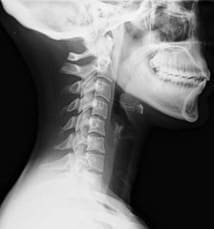

Les groupes pronostiques issus de cette règle sont classés à risque faible, moyen et élevé, déterminés à l’aide des scores de coupure du Neck Disability Index et de l’âge du patient. Cette règle détermine une récupération totale, récupération avec complication modéré, récupération avec séquelles.

Cette étude menée par Joan Kelly, Carrie Ritchie et Michele Sterling, Queesland Australie, cherche à présent à en étudier la corrélation entre un examen clinique classique et le pronostic qui en découle avec le jugement issu de la règle de prédiction. Ceci pour vérifier que la règle est plus pertinente qu’un examen classique.

le physiothérapeute traitant (n = 24) a classé le risque de récupération chez 38 adultes atteints de Wiplash aiguë à la fin de la consultation initiale. Un Kappa pondéré de Cohen a examiné l’accord entre la classification du risque estimé par le physiothérapeute et la Règle de prédiction de Ritchie C.